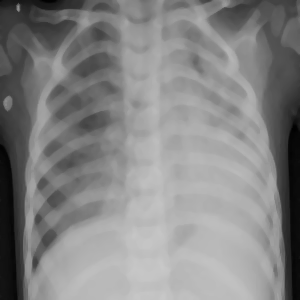

CLAHE